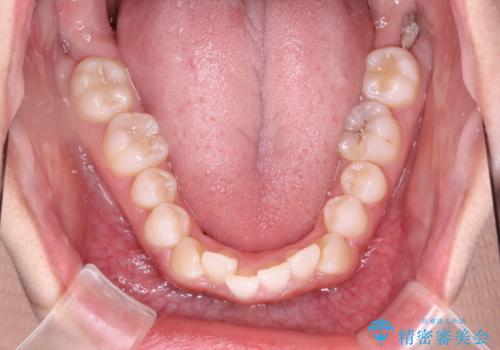

- 初診時には前歯部に捻転や叢生、臼歯部にも一部叢生が見られる状態でした。

インビザラインでの治療を計画し、行っていきました。

インビザライン治療により、捻転を含む歯列もしっかりと改善しています。

基本的な不正咬合部分は初回の30枚のマウスピースでほぼ改善しており、リファインメントでは前歯部の細かな調整など、患者様の要望を取り入れる形でシミュレーションをセットアップし、満足の行く結果に仕上がりました。